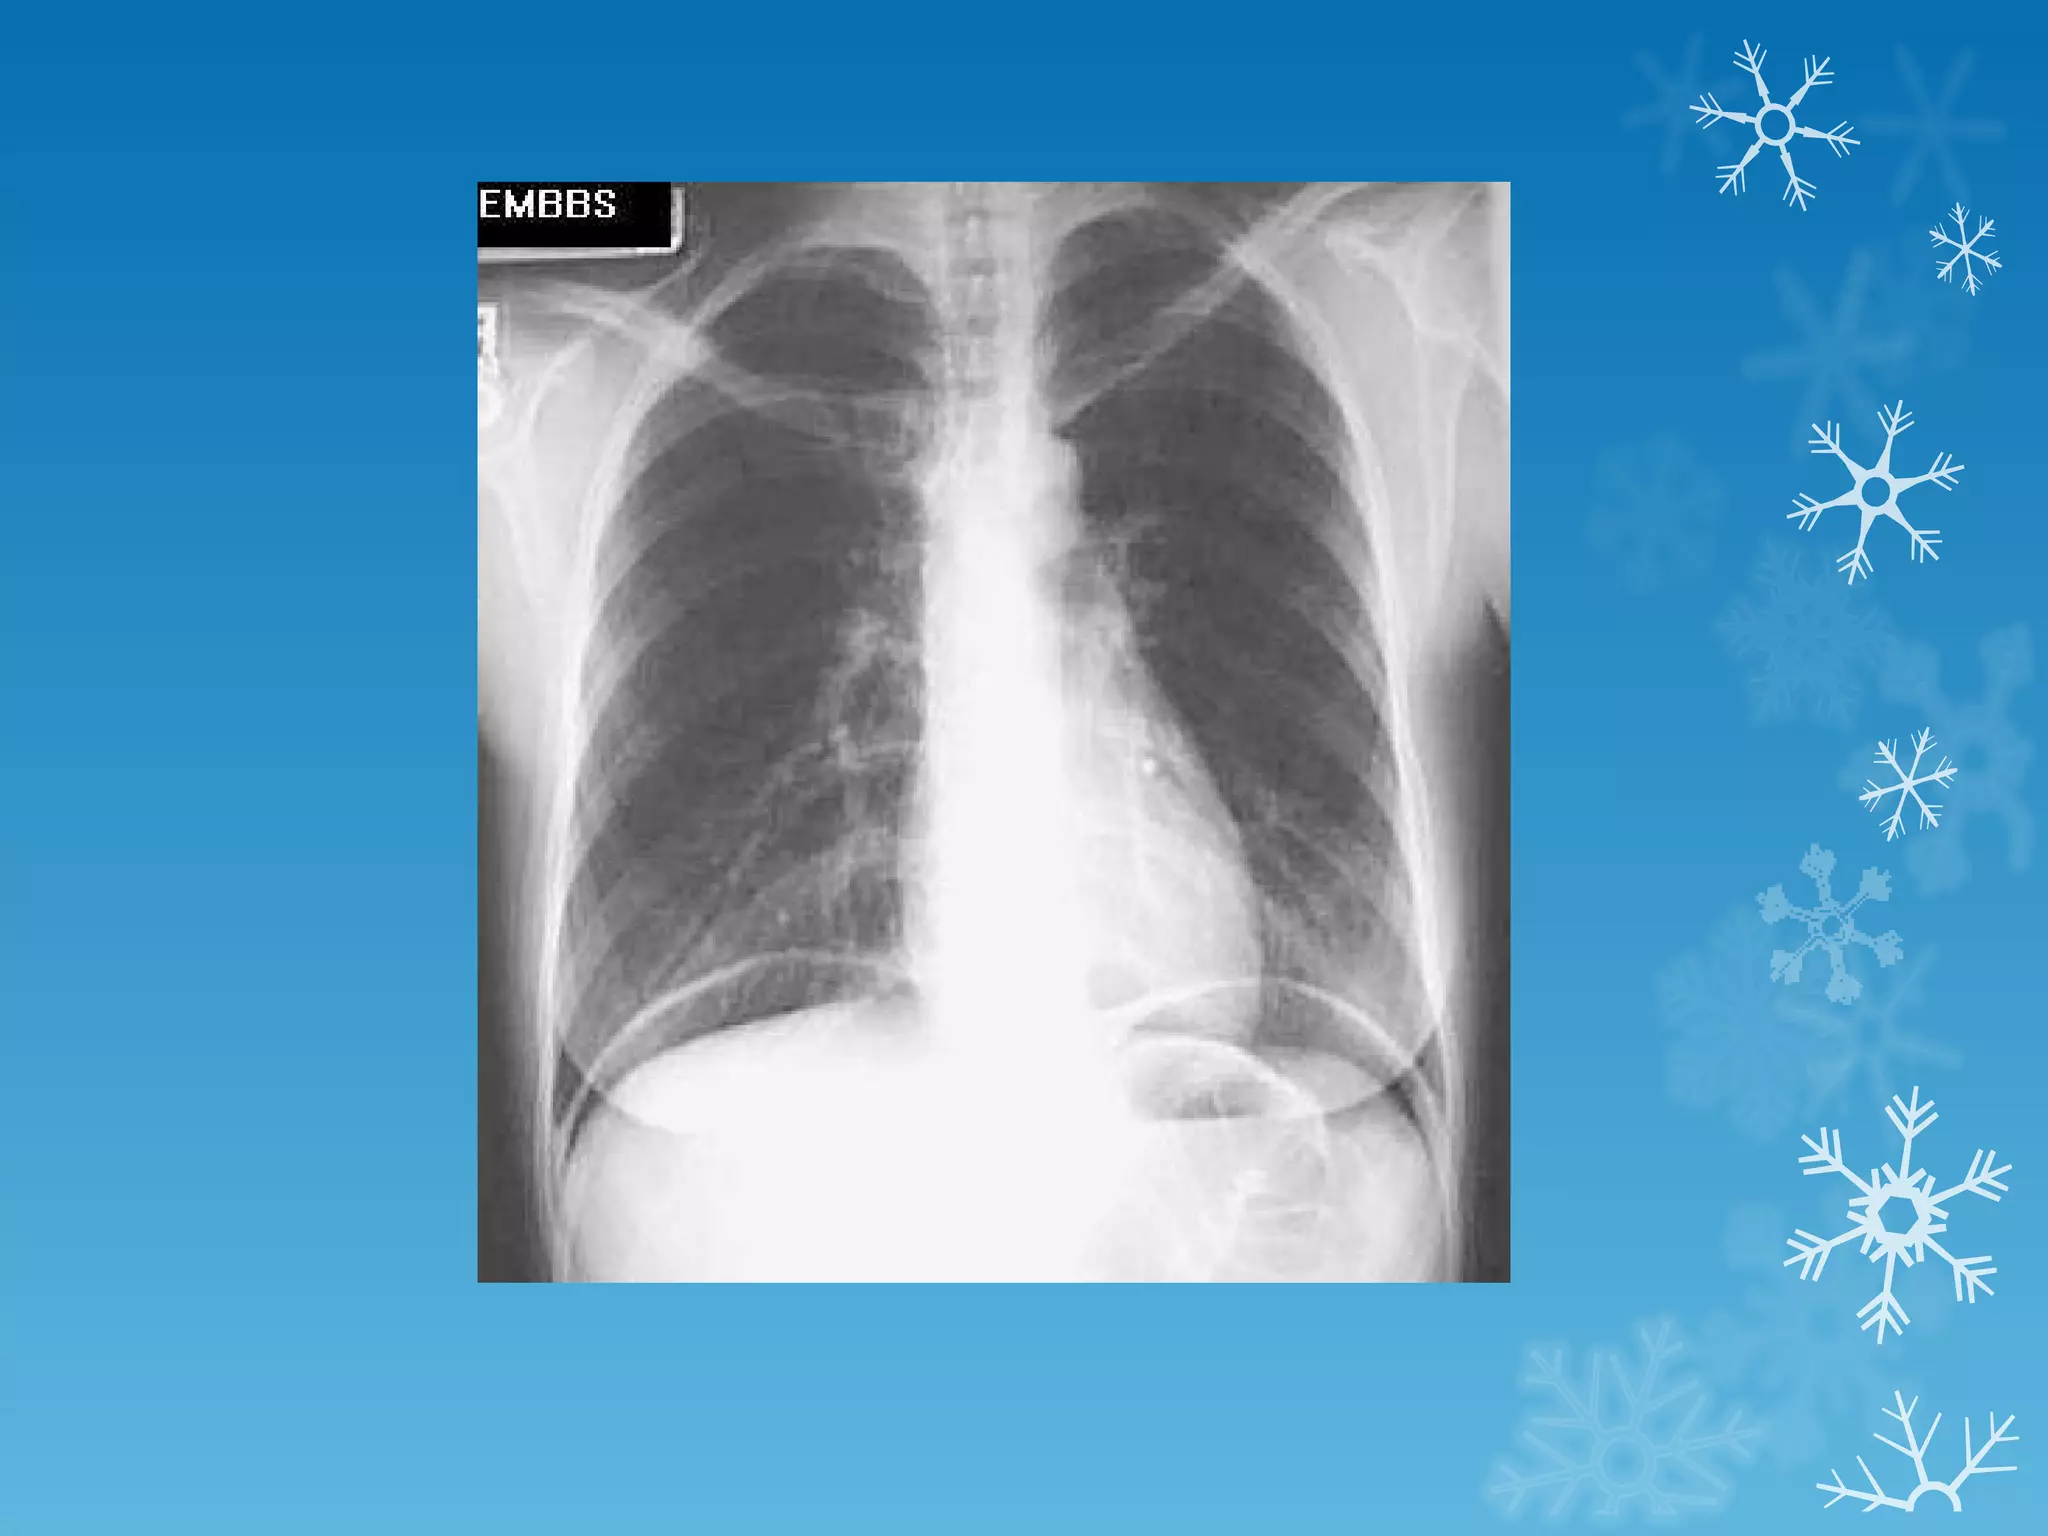

This document discusses chest x-ray interpretation and provides guidance on evaluating x-rays. It explains that tissue density determines how an x-ray beam penetrates, with denser tissues appearing whiter and less dense tissues appearing blacker. It also outlines different chest x-ray views and factors to consider like patient orientation, age, gender, and rotation. Abnormalities are described as appearing too white, too black, too large, or in the wrong place. The document stresses a systematic approach of identifying, localizing, describing lesions, and providing differential diagnoses.